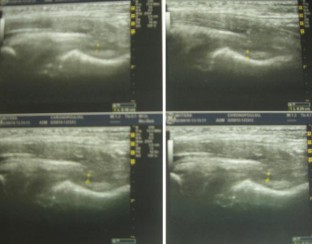

Inflammatory or septic arthritis due to Mp is an extremely unusual manifestation in children, and the functional outcome of the joints is difficult to be predicted. Two cases with Mp infection are presented. The first patient had positive PCR for Mp after hip aspiration and arthrotomy with thorough irrigation and debridement. A flattened femoral head was detected during the follow-up, which became quite spherical a year after. An arthrotomy with medial synovectomy of the knee was performed in the second patient. Lack of full knee extension was presented during the first 3 months, which gradually decreased to 7° in the final follow-up. The suspicion of Mp infection with extra-pulmonary involvement in children is mainly based on clinical, epidemiological and radiological data, but laboratory testing is required for confirmation. Rapid diagnosis of probability consists of serum tests, and their results are essential for early therapeutic planning. The direct diagnosis of Mp DNA through polymerase chain reaction (PCR) provides specificity and sensitivity. Very few cases of arthritis associated with Mp infection have been published but not with the severity of our cases. Clinical suspicion of Mp infection is of great importance, and the outcome depends on early diagnosis and specific treatment.

Fig. 2